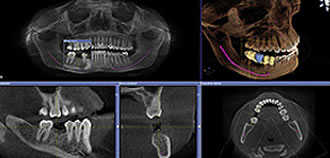

歯科用CTは、あごの骨を3次元の画像で処理できるため、神経の位置を把握したり、インプラントの植立、方向など念密な治療予測シュミレーションを行うことが可能です。 そのため、安全で、精度の高い手術を行うことが可能です。

そのシュミレーション画像を用いることで、医療情報の説明の分かりやすさも大幅にアップします。

以前は総合病院でCT撮影を依頼していたため、病院に出向く時間と費用がかかりましたが、CT導入の結果、撮影時間15秒、画像構成3分程度という驚異的な時間の短縮が可能となり、即日治療に最も効果を発揮、超スピーディーな治療を実現できます。さらに付属のCAD/CAMハイテク医療機器との融合により、革新的な歯科医療を提供することも可能となっています。